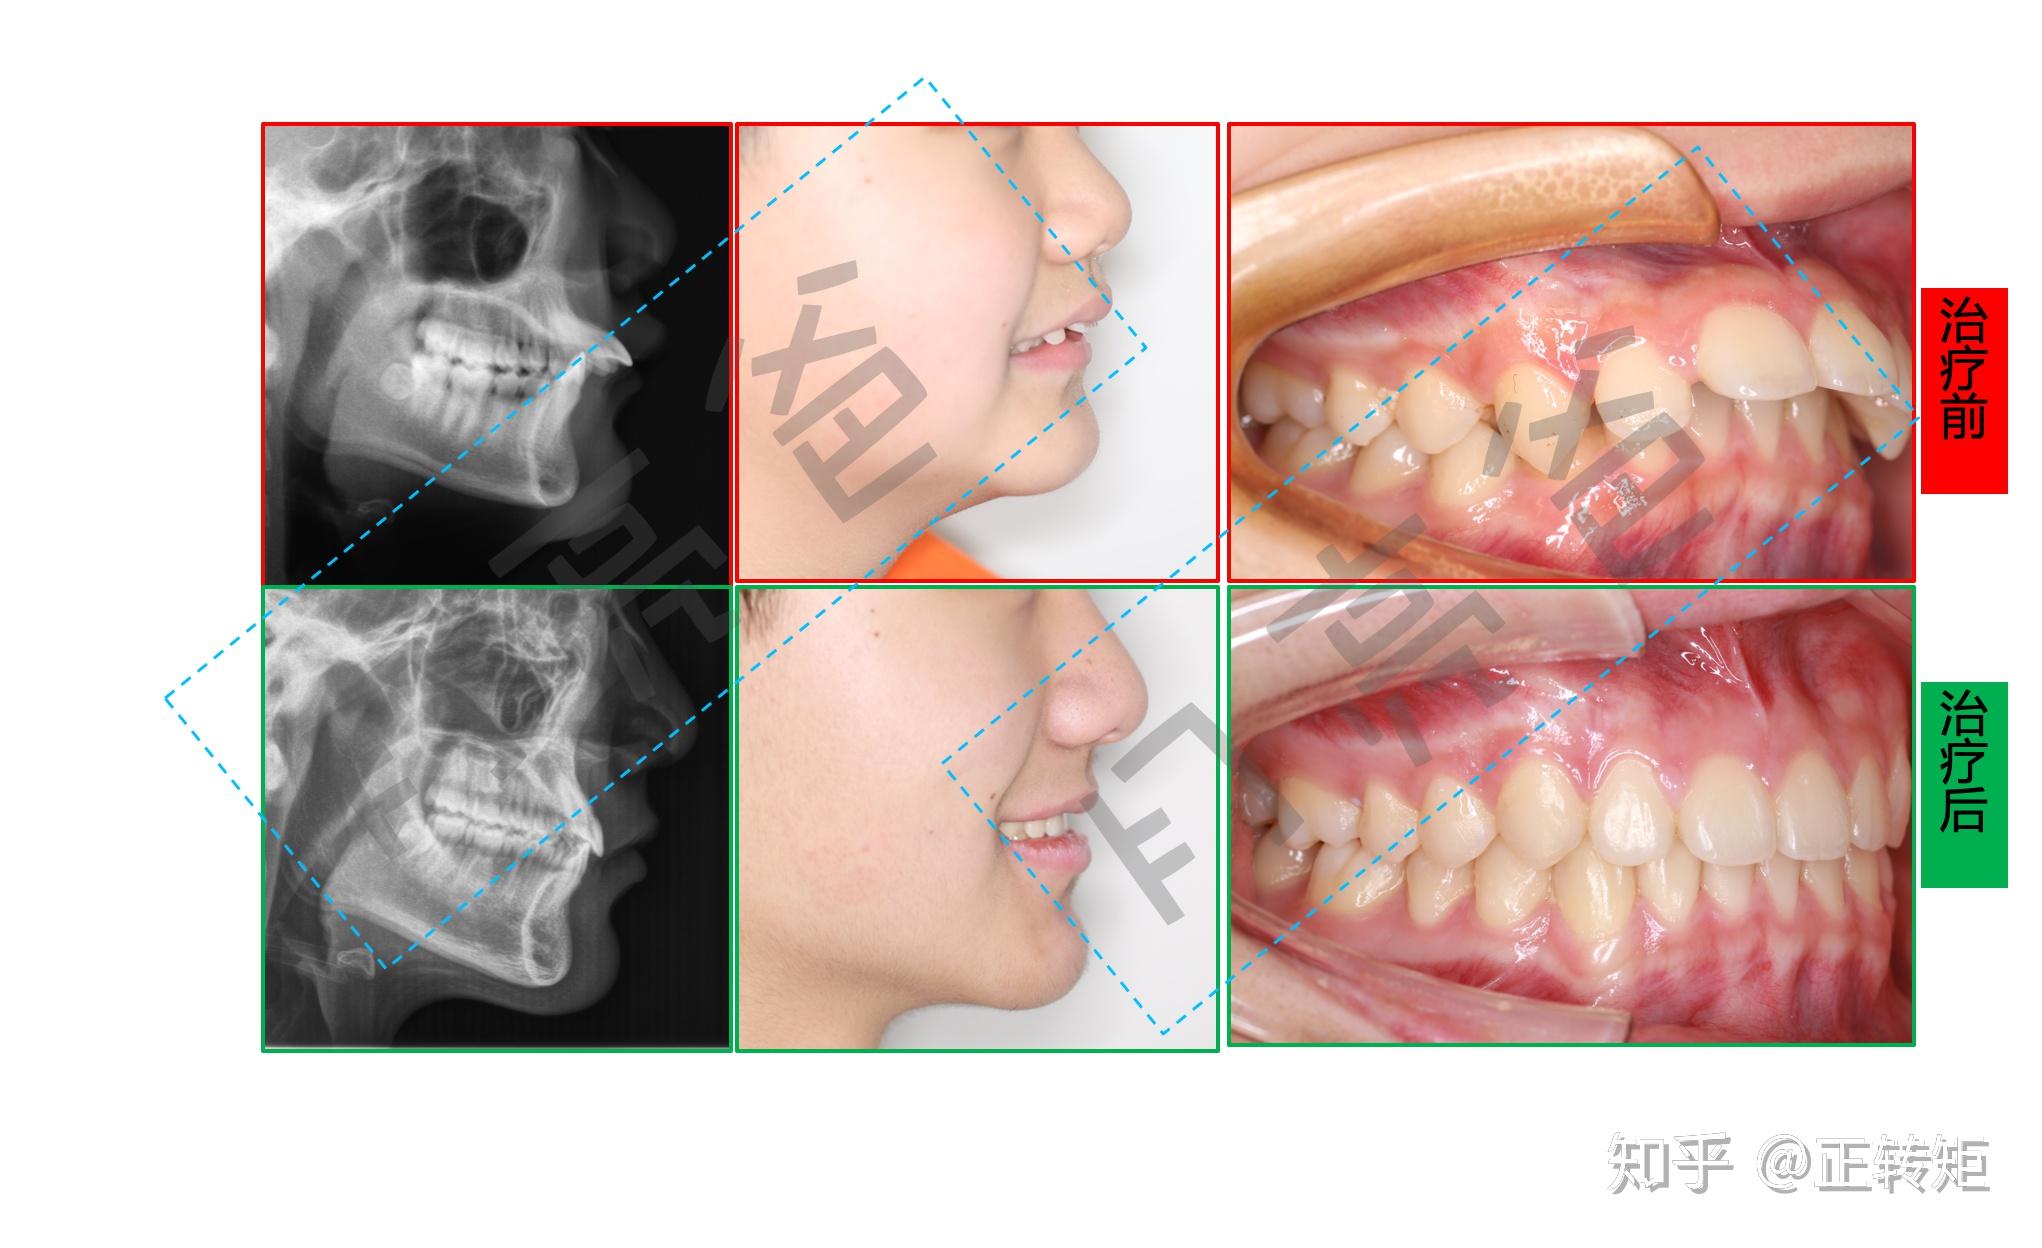

正畸治疗中的面型变化

治疗前后面相对比